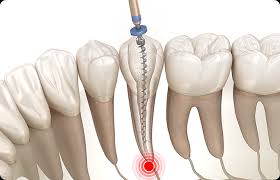

신경치료, 치료방법, 치료시간, 치료비용, 보험

1. 치과 신경치료란?신경치료(근관치료)는 치아 내부의 손상된 신경(치수)을 제거하고, 그 공간을 소독한 후 밀봉하여 감염을 막는 치료입니다. 충치가 깊어져 신경까지 침범하거나 외상, 감염